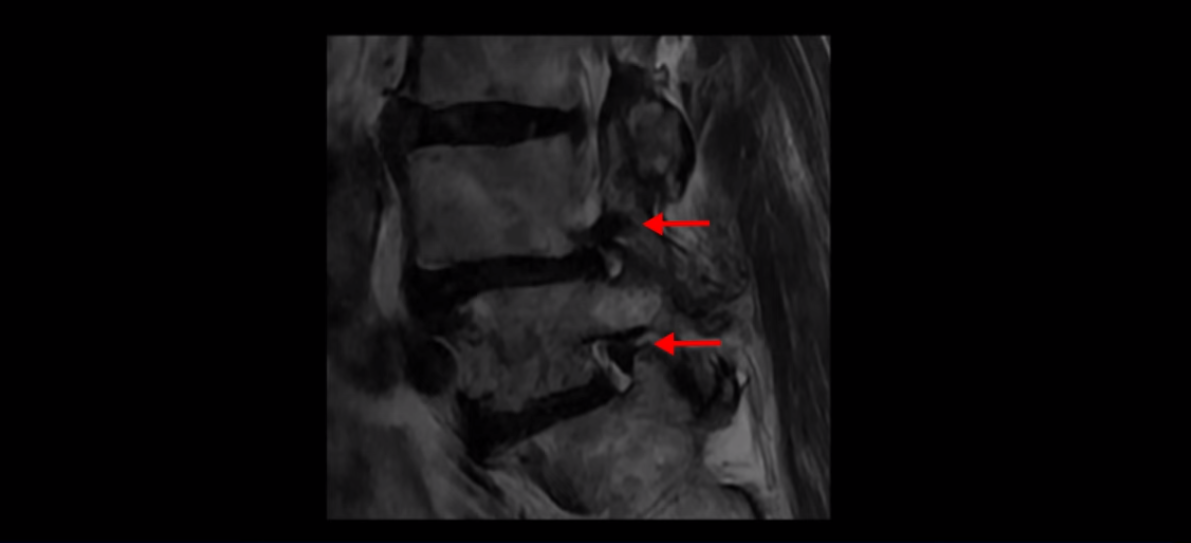

제가 먼저 이분 MRI를 보고 설명해 드린 후 어떻게 이런 분들을 수술 없이 허리 기능재활치료로 호전시킬 수 있는지 자세히 설명드리겠습니다. 이분 허리가 보시다시피 여러 마디가 퇴행되어 있고

4번 5번에는 뼈가 밀려 나간 전방전위증도 있습니다.

4번 5번 마디를 자세히 보면 심한 중심성 협착이 있어서 신경 구멍이 매우 좁아져 있습니다.

또 신경 가지가 빠져나가는 추간공도 매우 좁아져 있습니다.

그래서 양쪽 엉덩이가 아프고 다리는 발바닥까지 저리고 아프면서 발을 줄로 묶어놓은 것 같고 다리의 힘도 빠져 걷기가 어렵습니다.